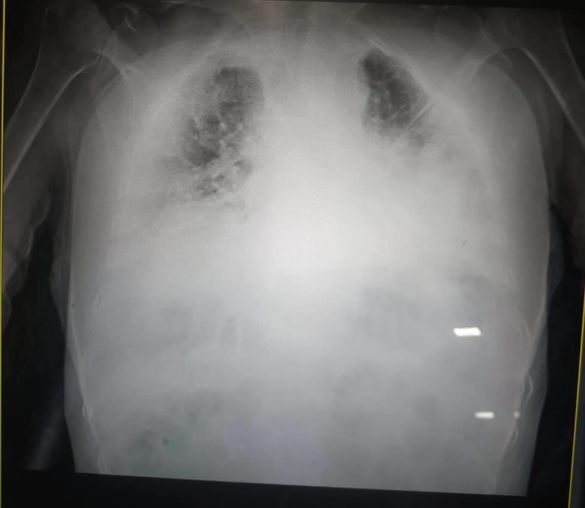

У Львові медики показали, який вигляд мають легені, уражені коронавірусом. Органи на світлині перетворилися на суцільну світлу пляму.

«Це одні з найстрашніших легенів, які я бачила в житті», – сказала мені щойно очільниця реанімації клінічної лікарні швидкої медичної допомоги Львова», – написала Ірина.

Нагадаємо, що патологоанатом розповів, як коронавірус змінює легені. Лікар говорить, що вони більше нагадують печінку.